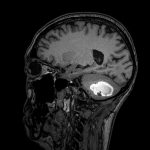

断層撮影

手術前1